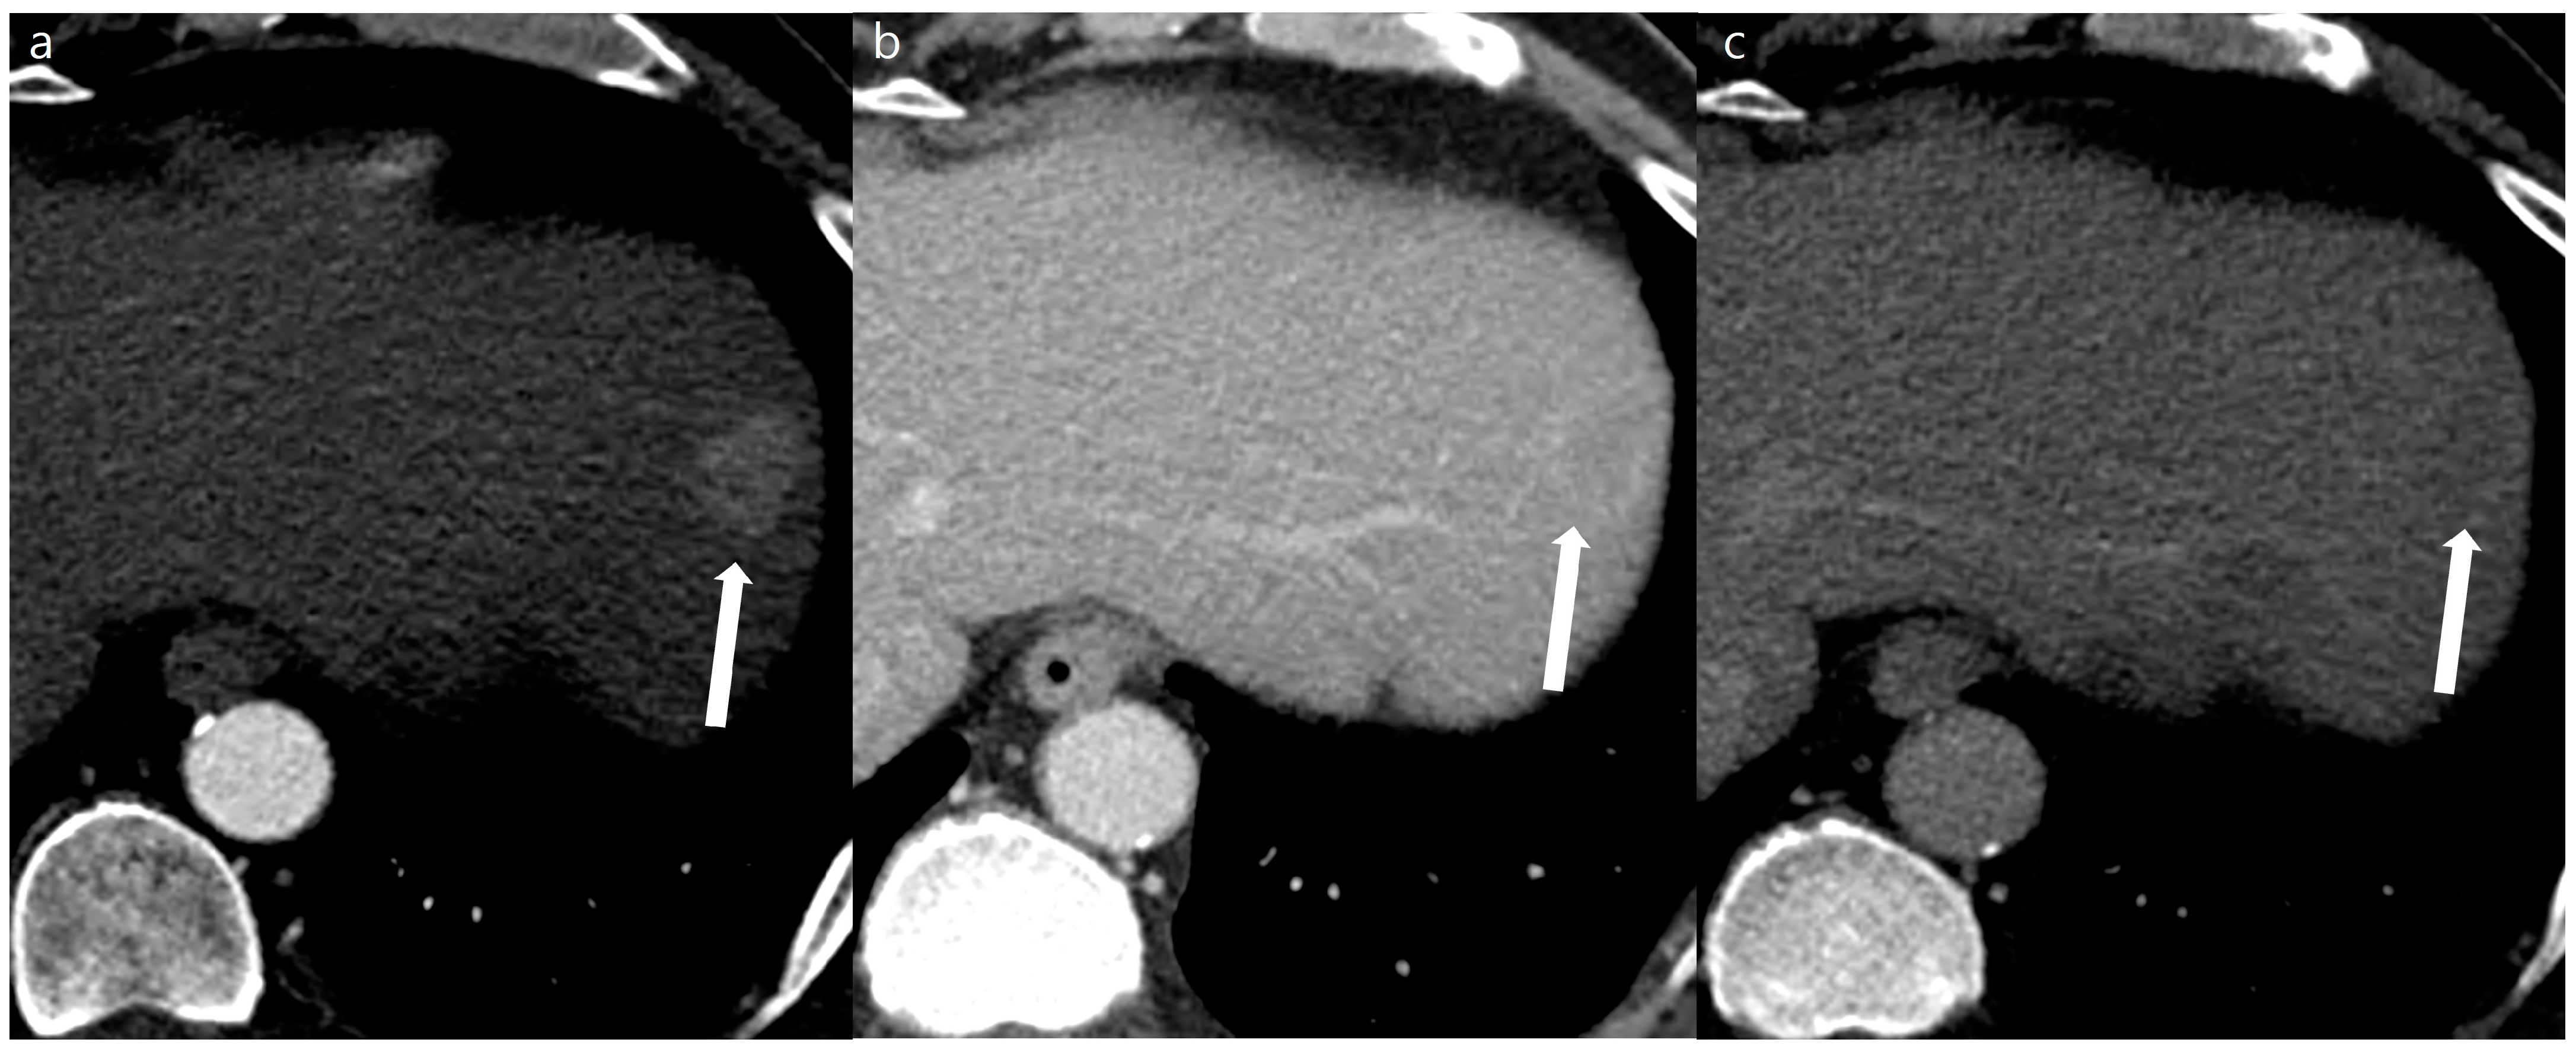

Figure 3. A 53-year-old man with a 2 cm sized hepatocellular carcinoma at segment 2 of the liver (arrows). Arterial phase (a), portal phase (b), and delayed phase (c) images of a standard-dose CT using hybrid iterative reconstruction show a well-enhancing nodule in the arterial phase (a), with washout on the portal phase (b) and the delayed phase (c).